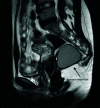

Figure 1.

Magnetic resonance image (Patient 5).